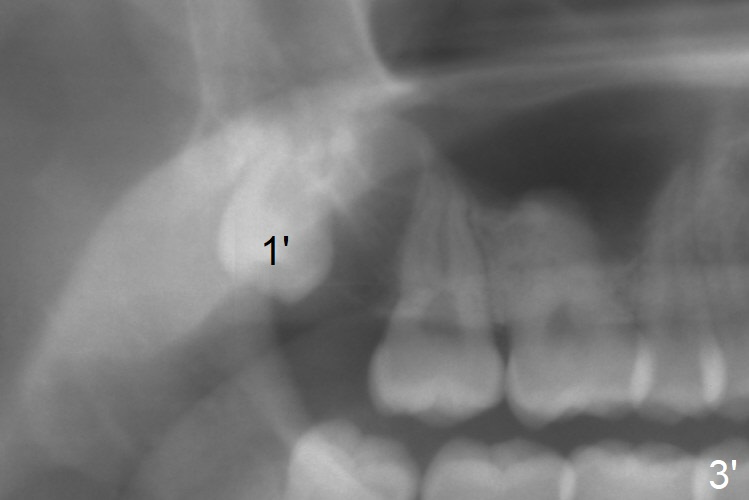

The 18 year old is a boy, whereas the 29 year old is a lady.  The former needs extraction; the latter ortho.  I love your wood vision, particularly the relationship between Le Fort I and sleep apnea.  I did think of Le Fort I initially.  I am afraid that it may be the last resort, if there is such a need.  Look at Fig.1',2'.

Panoramic X-ray is taken immediately post extraction of one of the upper right 3rd molars (Fig.3,3') and 20 months postop (Fi.4,4').  In fact the remaining one has erupted normally.